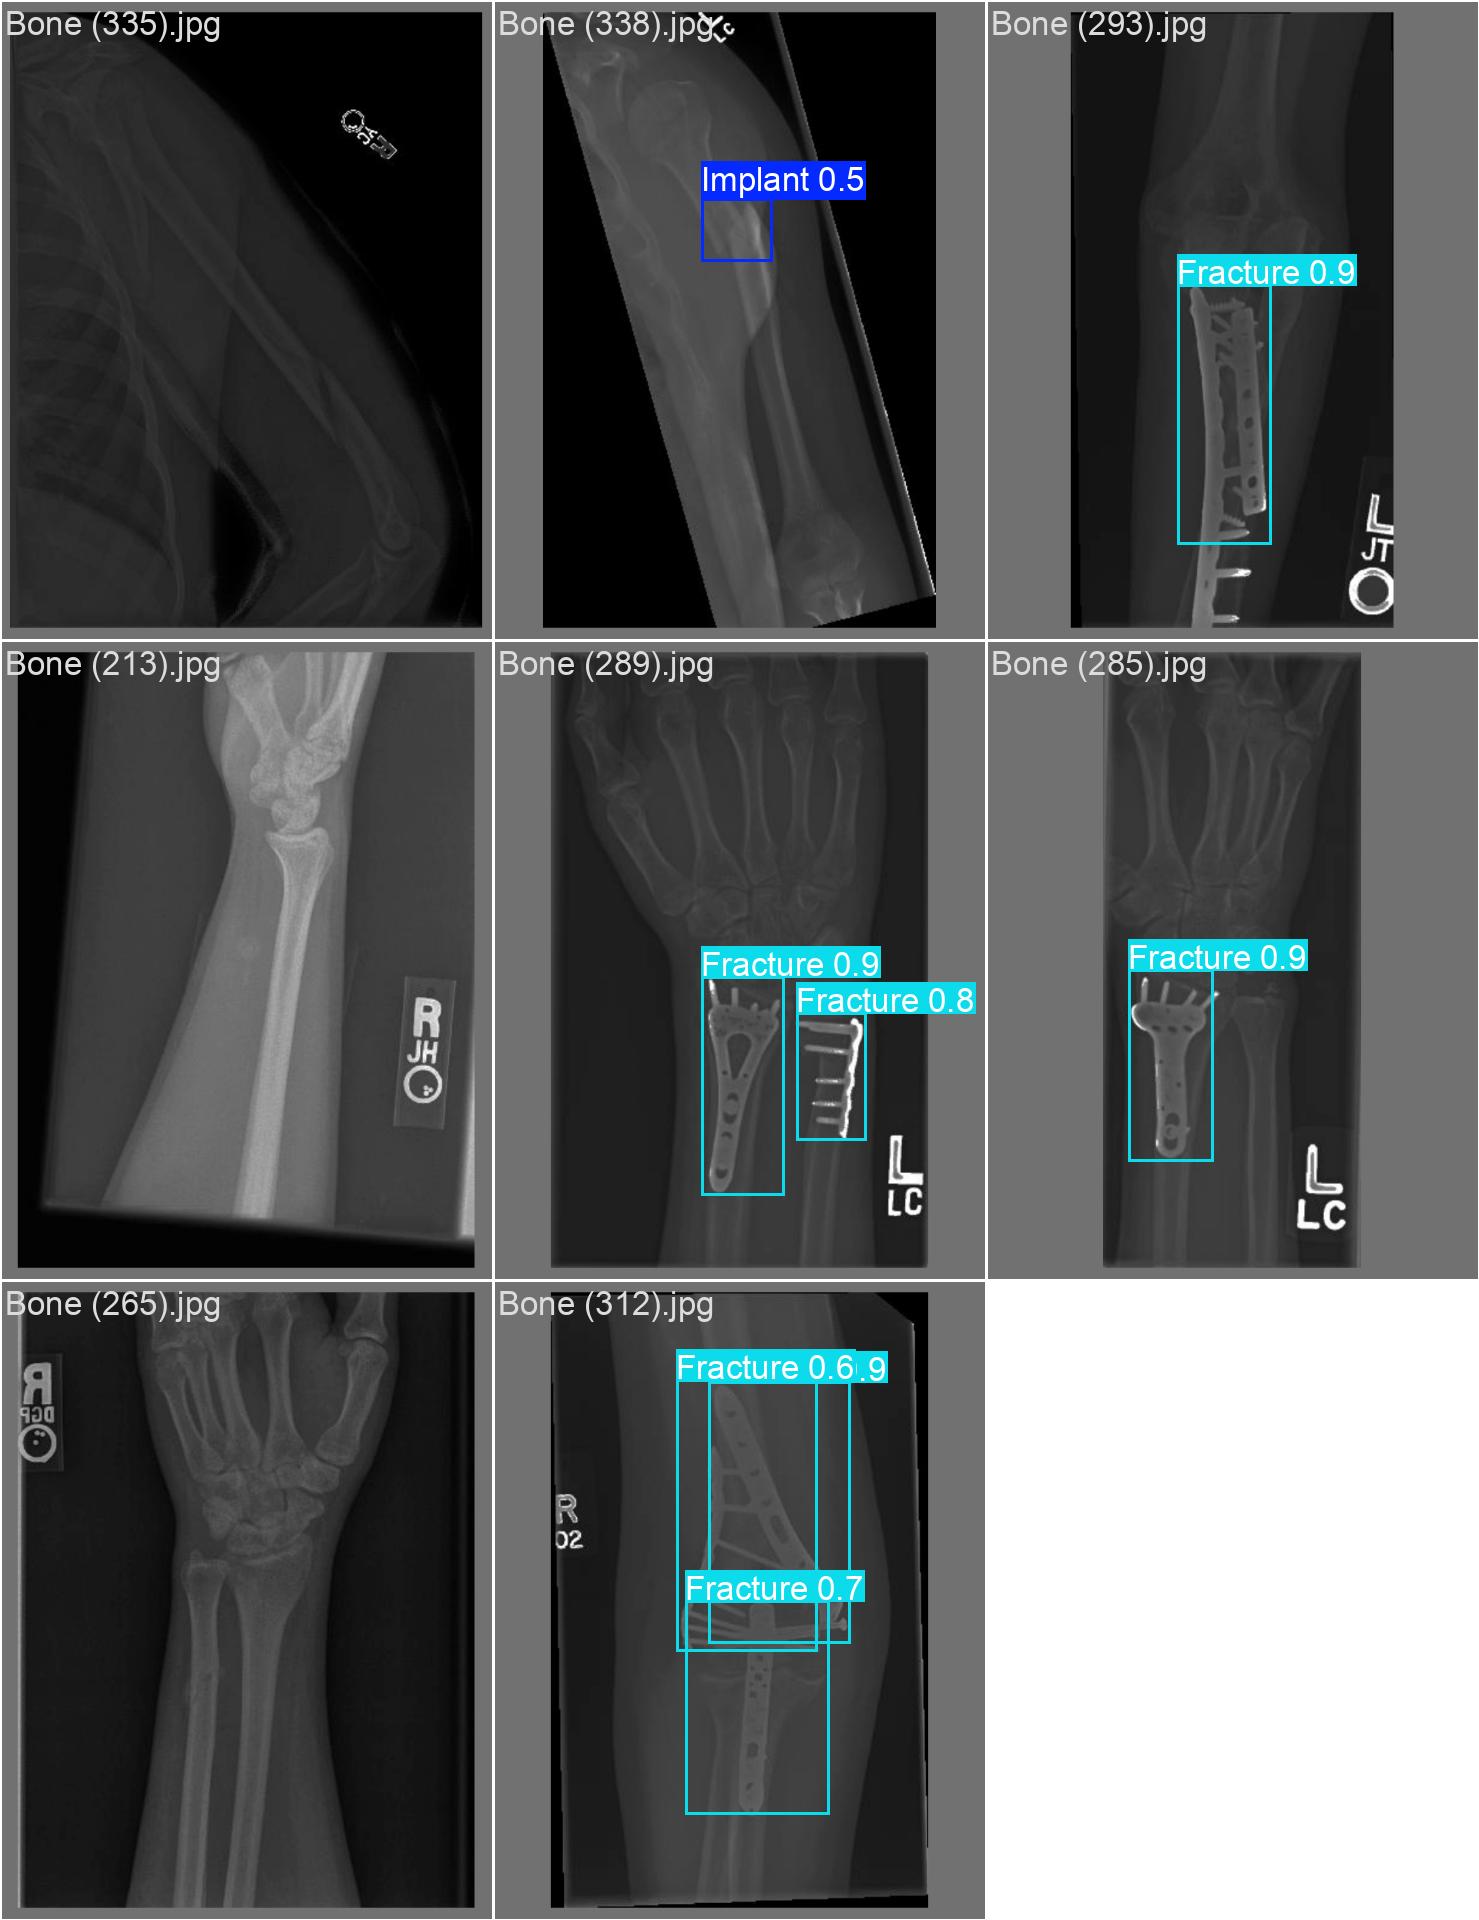

Bone 이미지 데이터 350장 중 Fracture 이미지 50장, Implant 이미지 50장, Bone 이미지 50장을 선별했다.

train과 val은 라벨링을 해야한다. 어제 라벨링을 했었지만, Fracture는 좀 넓게 잡고, Implant는 최대한 여러개로 쪼개는 느낌으로 라벨링을 다시했다.

20251204_01 predict

class 이름을 반대로 해뒀다...

| conf | 0.3 | 원래 0.9였는데 어제 결과가 너무 안 나와서 0.5로 바꿨다가 다시 0.3으로 바꿨다 |

20251204_02 predict2

진짜 라벨링 문제였나보다

그리고 predict 단계에서 IoU( Intersection over Union )를 낮추란다. 낮춰보자

20251204_03 predict

아 또 계정 바꾸면서 class 반대로 되어있는 파일로 넣었다

| conf | 0.3 | |

| iou | 0.5 | 줄여보기 |

아니 아까보다 더 안 좋아졌다.

20251204_04 predict2

class 반대로 되어있는 파일 수정 안 했다

| iou | 0.5 | 이것만 줄여보기 |

iou는 별로 효과가 없는 듯